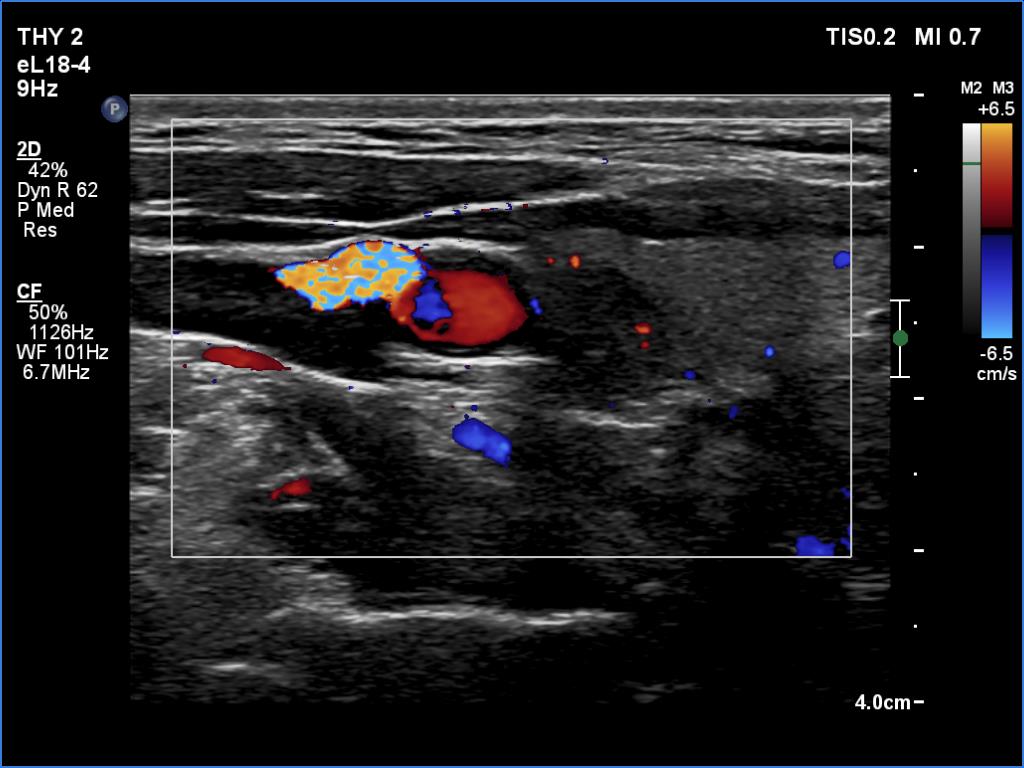

Right lobe, longitudinal scan

Right lobe, transverse scan, color Doppler mode. The nodule shows intranodular vascularity.